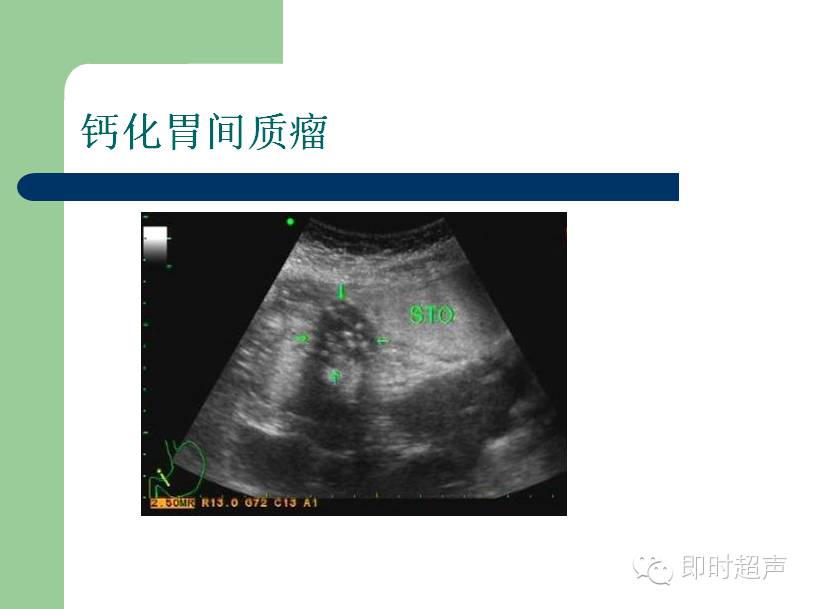

超声下的胃

来源:即时超声